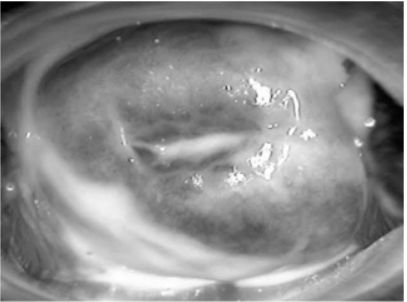

Uma gestante com dezesseis semanas e quatro dias compareceu ao pronto-atendimento com queixa de “corrimento vaginal” há quatro dias. O teste das aminas foi positivo e o exame especular é ilustrado na figura 1. Após a realização de coloração Gram, o resultado pode ser observado na figura 2.

Figura 1

Figura 2

Com base nesse caso hipotético, assinale a alternativa correta.